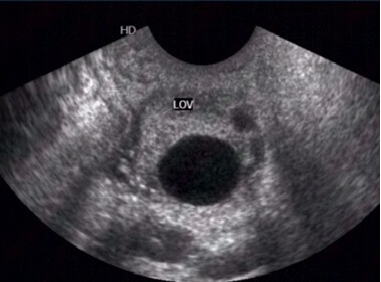

建议在排卵前2-3天和排卵后1-2天同房,就有可能受孕,这个时期叫易孕期或危险期。卵泡排出后的生存时间一般是8个小时左右,当B超检测卵泡在2.0cm以上时,即表明可能在48小时之内排卵,而精子排出后在体内的存活时间可以达到48~72小时,所以,当B超发现成熟卵泡,即可着手准备同房时机,超出12个小时以上,受孕的几率就相对降低了。